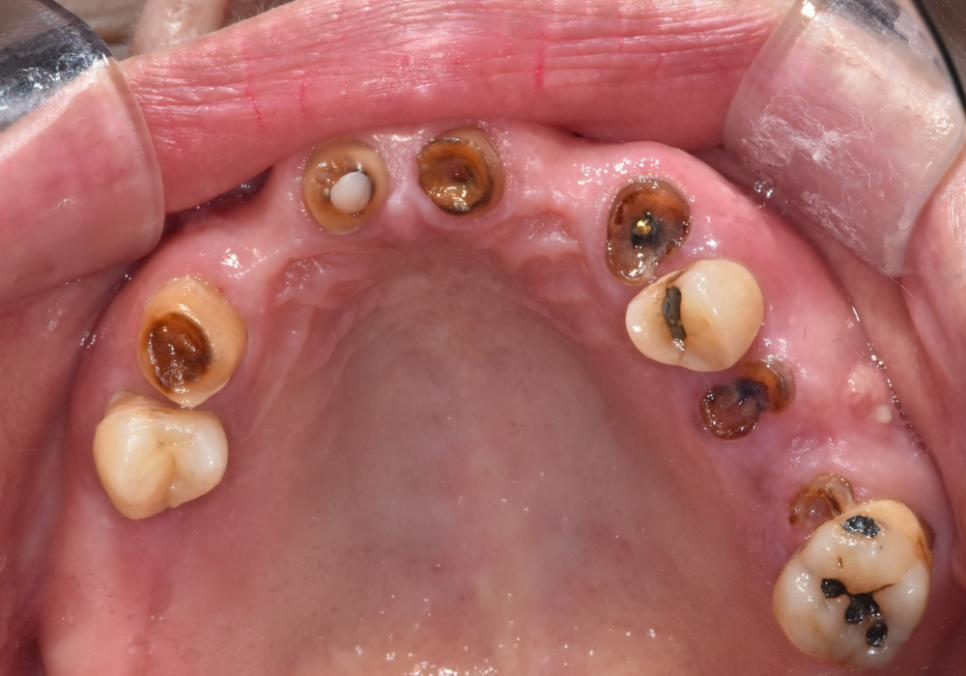

위턱은 대부분의 치아가

뿌리만 겨우 매달려 있었습니다.

가장 튼튼해서 살려 쓸 수 있는

위쪽 치아 2개(#14, 27)만 남기고

나머지는 안타깝게도 발치를 결정했습니다.

아래쪽 앞니들은 잇몸뼈가 많이 녹아 흔들리고 있어

총 4개의 치아를 발치하기로 했습니다.